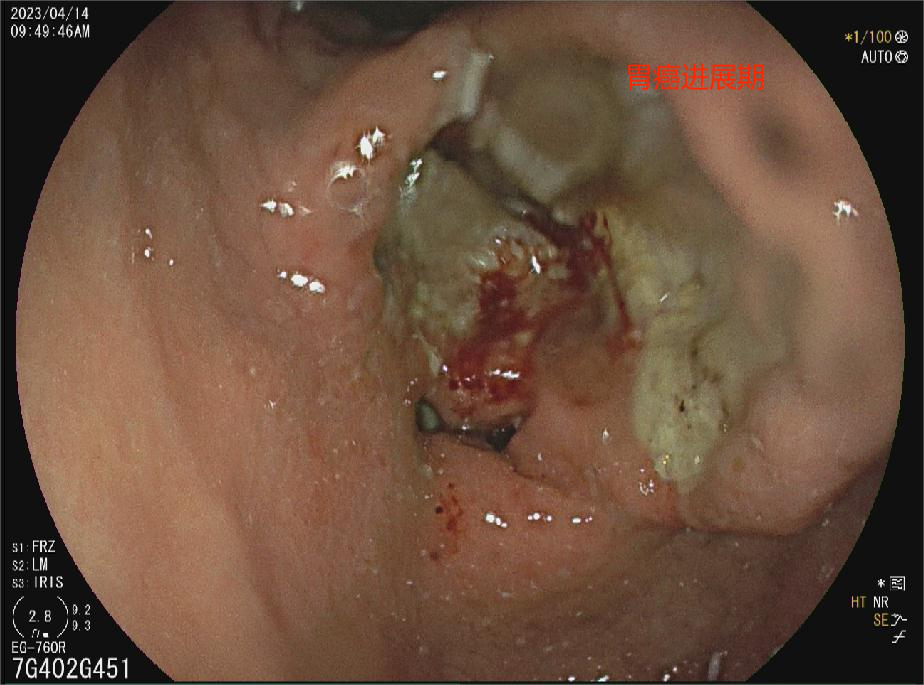

胃癌进展期